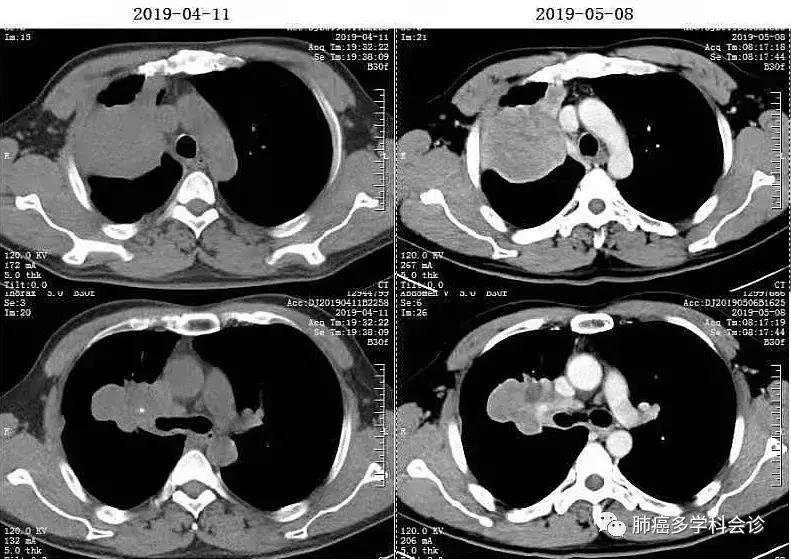

2019.4.12复查CT示病情进展,二线“多西他赛+奈达铂”化疗1周期。2019.5.8复查CT,提示病情稳定。患者不能耐受继续化疗。

患者同意参加“PD-1抗体(国产某公司生产)+安罗替尼”治疗NSCLC的临床试验(研究者发起)。于2019-05-09 开始进行“PD-1抗体+安罗替尼”治疗,之后不久,患者自觉双眼胀痛、心悸。2019-06-01查T3、T4均明显升高,抗甲状腺过氧化物酶抗体239.40IU/mL(0-155) ↑,抗甲状腺球蛋白抗体273.80IU/mL(0-34) 。彩超:甲状腺弥漫性回声改变伴血流增多,颈前VI区淋巴结肿大。